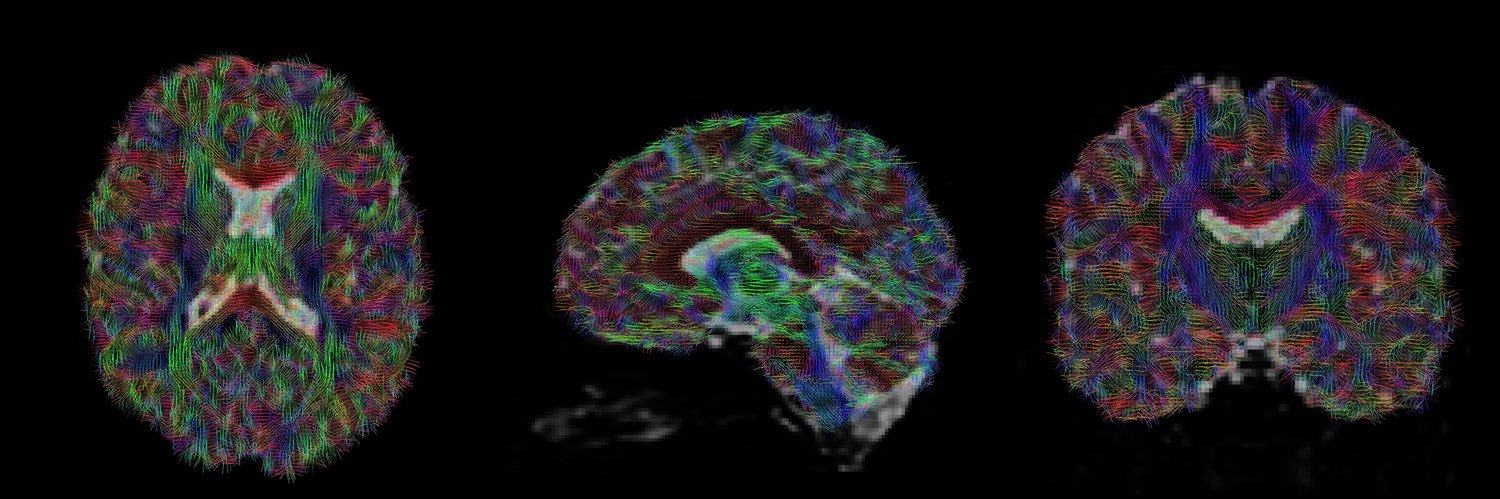

Our findings show microstructural fibre properties of the brain’s white matter do not differentiate recovered children from those with persisting symptoms. 🧠